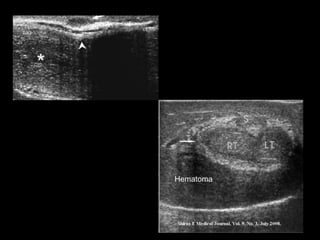

Diagnostico

• Clinica

• USG

• USG DOPPLER